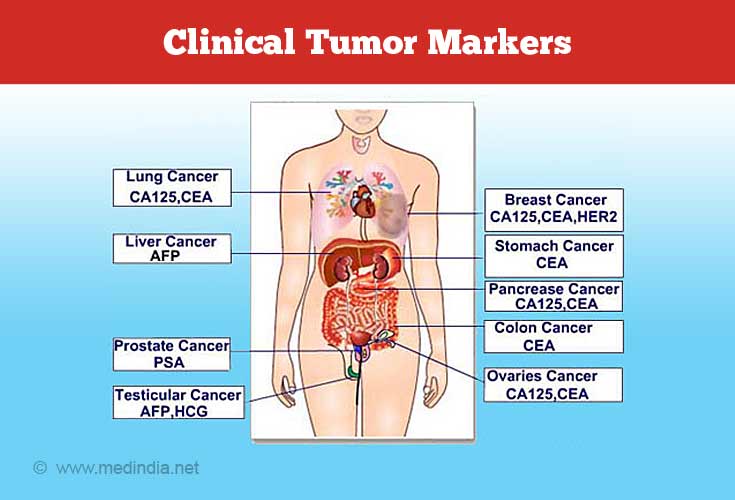

Tumor markers may be specific for a particular cancer or may be common to a few types of cancers. Alternatively, tumor markers may be present in non-cancerous conditions as well. In this case, these conditions should be ruled out before focusing on cancer. Research is still underway to identify specific markers for different types of cancers.

There are several markers that have been identified, but many had to be shelved due to their non-specificity. This is due to the overlap that occurs between different cancer tissues and the various markers produced by them. As a result, there are just a handful of markers that have been ear-marked by health-care specialists to be used as diagnostic or prognostic tools.

The most widely accepted tumor marker to date is the Prostate Specific Antigen (PSA) used in the diagnosis and management of prostate cancer.

Some of the common tumor markers and the associated disease conditions are discussed in the following sections.